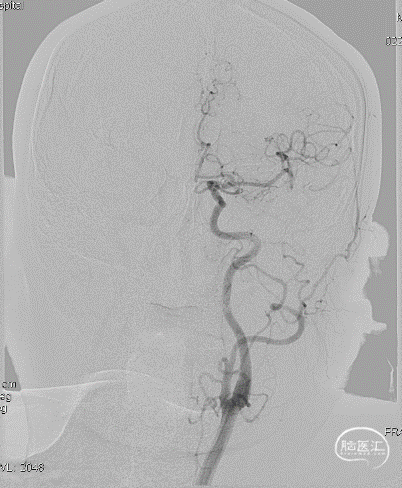

局麻,右股动脉入路置8F短鞘,导管导丝技术将8F MPA置于右C1末端,造影确认右M1急性闭塞,侧支代偿差。

以Transend导丝 + Headway21导管到达M1中段,Sofia PLUS顺畅到位(M1中段),ADATP技术抽吸取栓,一次成功取通,前向血流恢复至TICI3级,无栓子逃逸及原位狭窄,穿刺至开通时间20min(患者术中间断躁动不配合)。

开通右MCA后,行左侧颈动脉及左椎动脉造影显示血流通畅(双侧后交通动脉开放)。

右颈动脉再次造影见前向血流持续通畅,患者此时左侧下肢肌力恢复Ⅲ级、上肢Ⅰ级、语言功能好转,遂结束手术。

以Sofia Plus进行抽吸取栓1次(ADAPT技术),实现血流复通(TICI 3级)